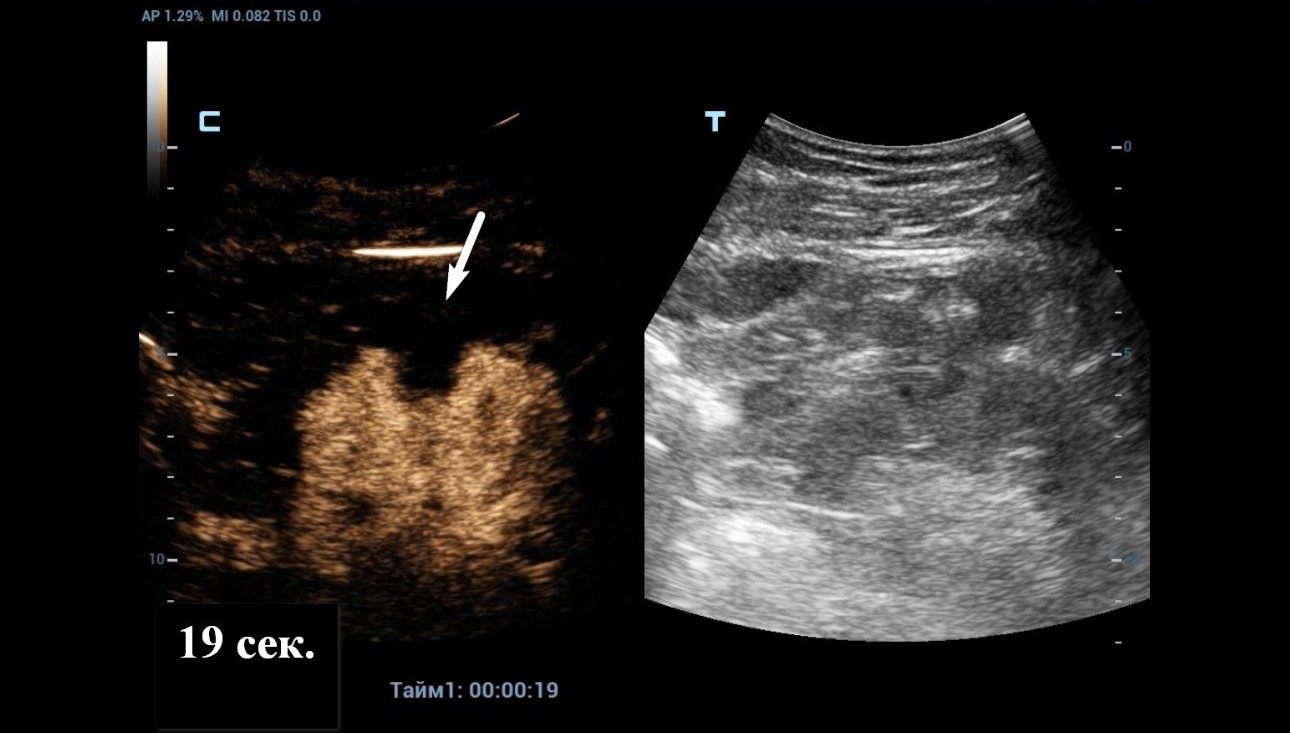

An ultrasound examination was conducted using a Resona 7 ultrasound machine (Mindray, China) with the SC5-1U transducer. A cystic lesion measuring 46x35 mm in the middle part of the right kidney was found with multiple septa measuring up to 2 mm thick. When scanning the right kidney, a cystic mass with clear, even contours, 46 x 35 mm in size with multiple thick partitions (about 4 partitions) is visualized in the middle part of the cortex. It is homogeneous and anechoic within the cystic mass. A hyperechoic node measuring 10 mm in length was seen protruding into one of the cystic partition (Figure 1 and 2).

As Power Doppler showed indeterminate results regarding internal flow within the complex cystic mass, CEUS was performed through injection 1.2 ml of Sonovue (Bracco Swiss, SA, Switzerland). The longitudinal plane of the kidney with the maximum section of the cystic mass was selected for scanning. At the end, the cystic mass was characterized as benign by a lack of enhancement throughout the CEUS study (Figure 4 and 5).